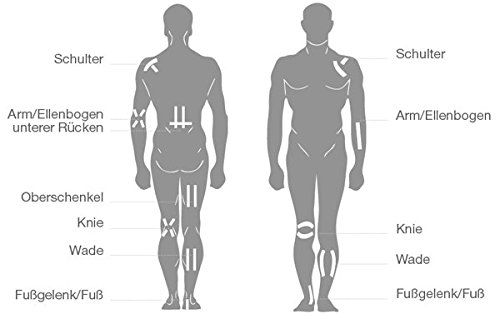

Kullanım Alanları

- Rehabilite edilmek istenen bölgeye hem kinesyolojik tekniklerle hem klinik bantlama teknikleriyle uygulanır.